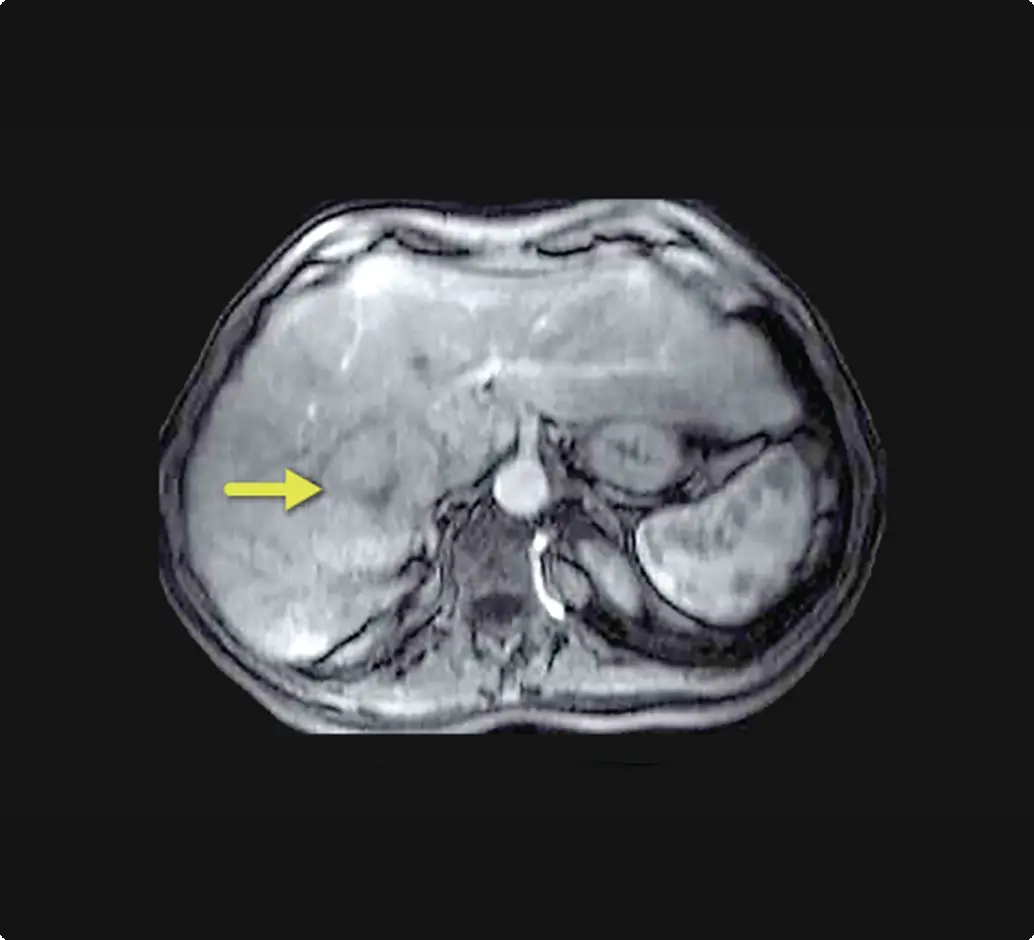

Reduced vascularity limit pathways to penetration

It can be challenging to achieve adequate particle penetration into tumors with minimal or absent enhancement due to reduced vascularity.6